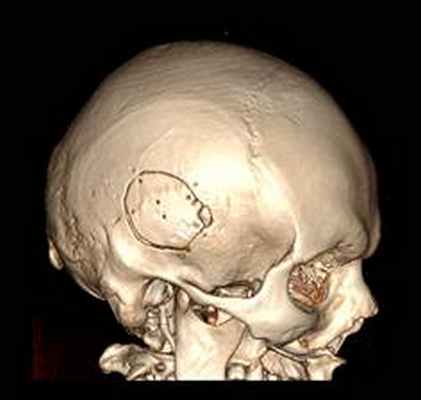

КТ головного мозга с контрастным усилением (24.03.2015): объемное кистозно-солидное образование правой теменно-височно-лобной области. Дислокационный синдром.

22.10.2015 была выполнена операция: микрохирургическое удаление опухоли правой височной доли под интраоперационными навигационным контролем и с интраоперационной фотодинамической терапией.